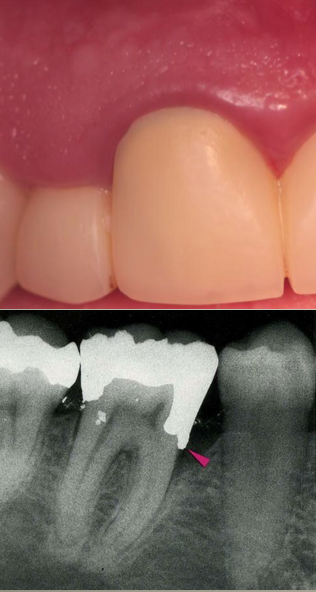

Biologic Width Violation

On the mesial surface of the left central incisor, bone has NOT been lost, but gingival inflammation occurs.

On the distal surface of the left central incisor, bone loss has occurred, and a normal biologic width has been reestablished (one possibility)

The signs of biological width violation

chronic progessive gingival inflammation around the restoration

BOP

localized gingival hyperplasia with minimal bone loss

gingival recession

pocket formation

clinical attachment loss

gingival hyperplasia is most frequently found in altered passive eruption and subgingivally placed restoration margins